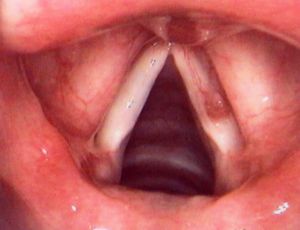

(2)喉鏡檢查:聲帶息肉多一側呈灰白色或淡紅色光滑的贅生物,有蒂或廣基或瀰漫性聲帶邊緣呈灰白臘腸狀腫塊。